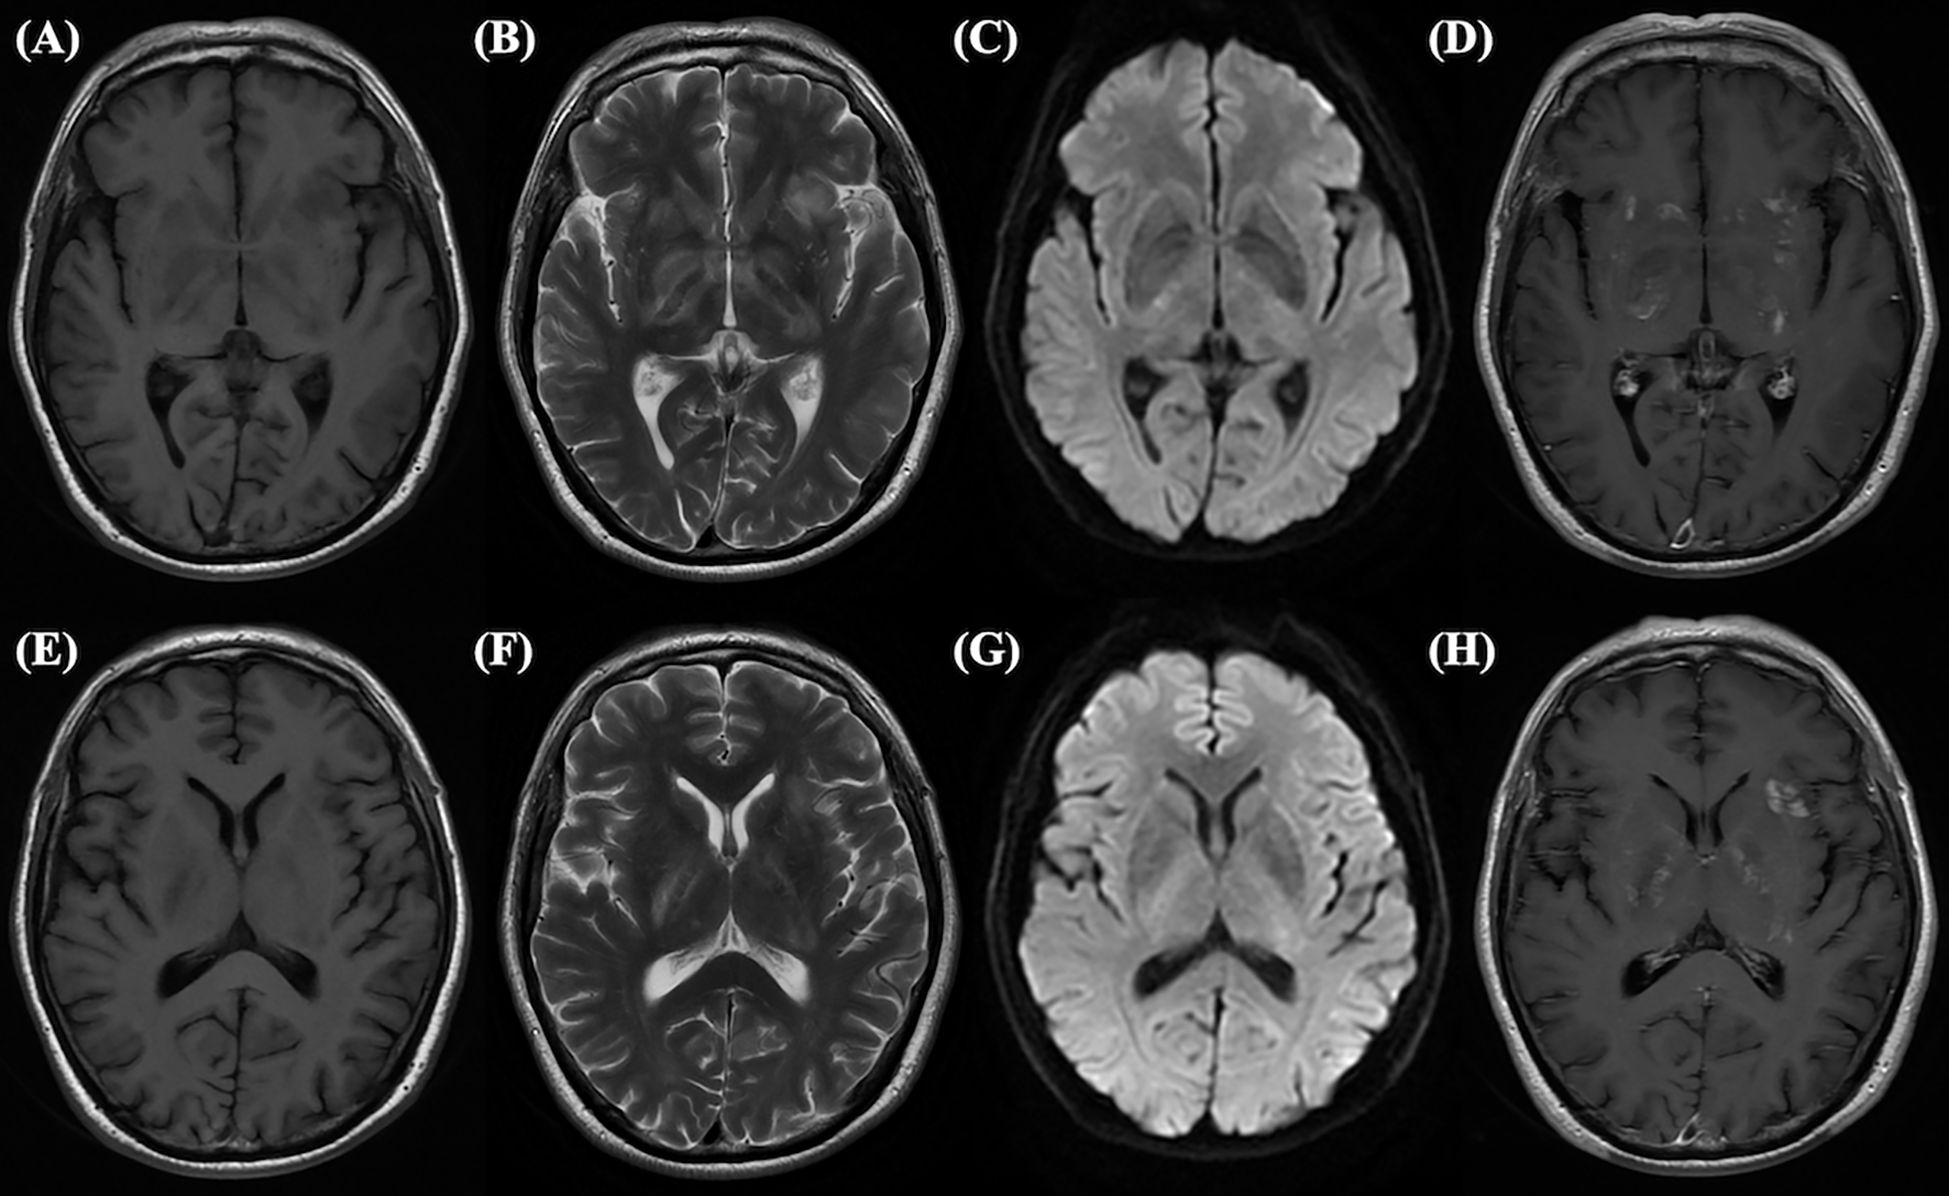

Figure 2

Four MRI brain scans labeled A to D, showing different contrasts and details. Image A has high contrast with bright areas in the eyes. Image B is darker with more uniform shading. Image C shows distinct bright and dark regions in the brain's structure. Image D has a balance of contrast, highlighting certain brain regions.

Figure 2. This abnormal MRI was from a 28-year-old male suffered from NMDARE then transferred to MOGAD. Axial T2-weighted (A) and enhancement (B) images showed hyperintense signals in brain pons, bilateral middle cerebellar peduncle and medulla oblongata at the first relapse. At the second relapse, left cerebellopontine area showed hypersignals in T2-weighted (C) and enhancement (D). Both relapses were double antibody positive.

In our study, patients with positive MRI findings exhibited overlapping manifestations of MOGAD and anti-NMDARE, such as involvement of the cerebral cortex, basal ganglia, and brainstem, (Figures 2, 3), which is consistent with previous studies (5). Patients with anti-NMDARE typically show normal or mildly abnormal MRI findings, presenting as scattered cortical or subcortical T2-weighted hyperintensities, with a few cases showing inflammatory demyelinating changes involving the brainstem and white matter (14). In contrast, MOGAD involved more extensive imaging abnormalities, affecting the cortical grey matter, subcortical white matter, deep white matter, brainstem, basal ganglia, thalamus, and cerebellum, presenting as poorly demarcated hyperintensities on T2-weighted images (20, 21).It has been suggested that when anti-NMDARE patients present with positive imaging findings, especially demyelinating changes in the white matter and infratentorial regions, the presence of MNOS should be considered. The MNOS group showed a higher rate of brainstem involvement on MRI than the anti-NMDARE group. Previous research indicated that the brainstem is the most frequently involved brain structure in MNOS patients (5).